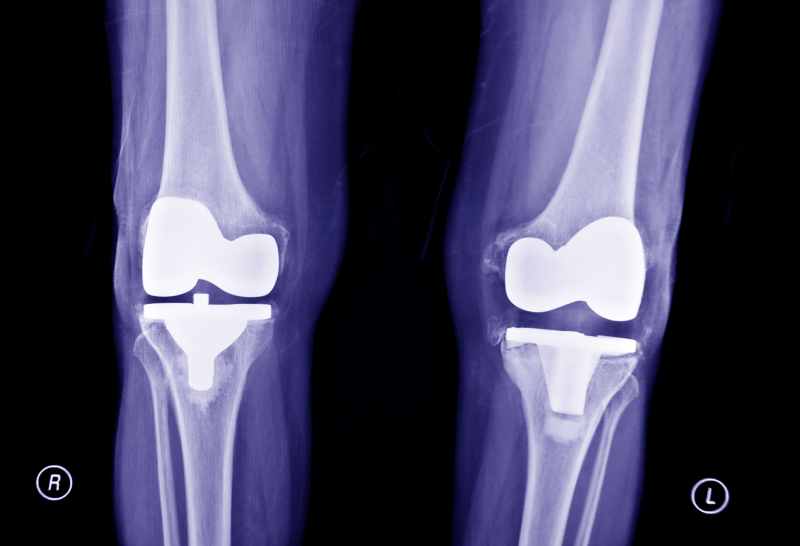

When your child gets hurt, you want answers quickly. X-rays help determine if an injury involves a fracture, dislocation, or other internal issue that cannot be seen from the outside. Having on-site imaging ensures children get the right diagnosis and treatment without the delays of outside referrals. At Super Kids Urgent Care, we provide safe, accurate pediatric X-rays in a child-friendly setting.

X-rays help identify the cause of pain or swelling and confirm an injury. Some common reasons we perform X-rays include:

Our providers use X-rays to make accurate diagnoses and create effective treatment plans.